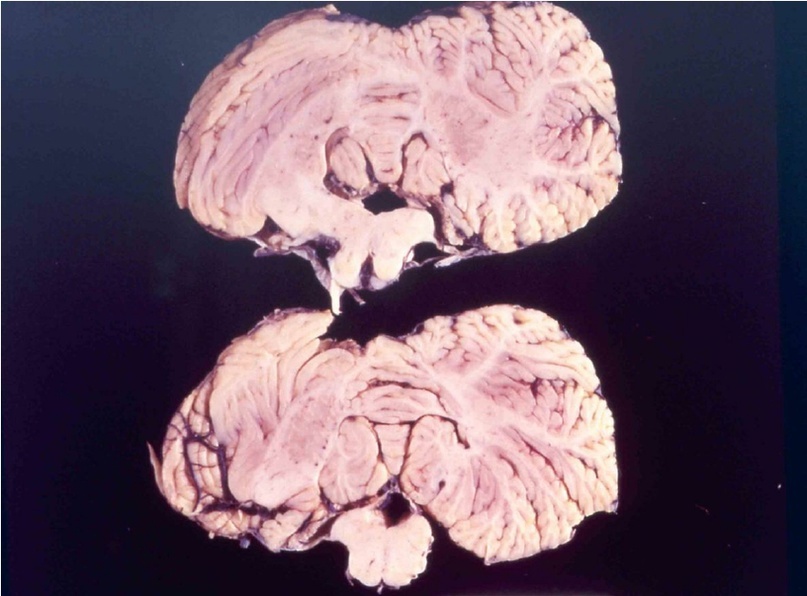

При болезни куру патологические изменения можно наблюдать только в центральной нервной системе. Обычно они выражаются в формировании типичной губчатой энцефалопатии. В коре, подкорковых ядрах, подбугорной области и в мозжечке наблюдается вакуолизация дендритов, аксонов и тел нейронов. Вакуолизация становится настолько выраженной, что серое вещество коры большого

головного

страдавшего от болезни

взрослого мужчины,

который впоследствии

погиб от куру

Изменения нейронов сочетаются с гипертрофией и размножением астроцитов. При куру у человека патогистологические изменения наиболее выражены в мозжечке: появляются аморфные ШИК-положительные бляшки, содержащие амилоид, уменьшается количество грушевидных нейронов (клеток Пуркинье). Вместе с тем, при куру не удаётся обнаружить воспалительной реакции, столь характерной для многих заболеваний ЦНС, или таких характерных признаков вирусной инфекции, как образование телец включений или глиальных узлов.

Характерные для куру изменения ЦНС обнаруживаются ещё до появления клинических симптомов заболевания, что сопровождается снижением общего содержания ганглиозидов в сером веществе головного